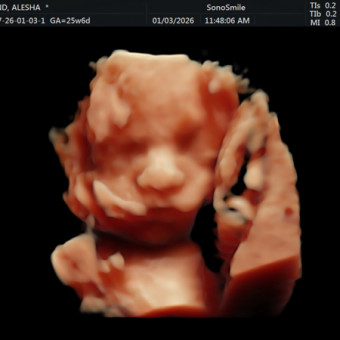

Alesha Roland

The Villages, FL

April 10, 2026